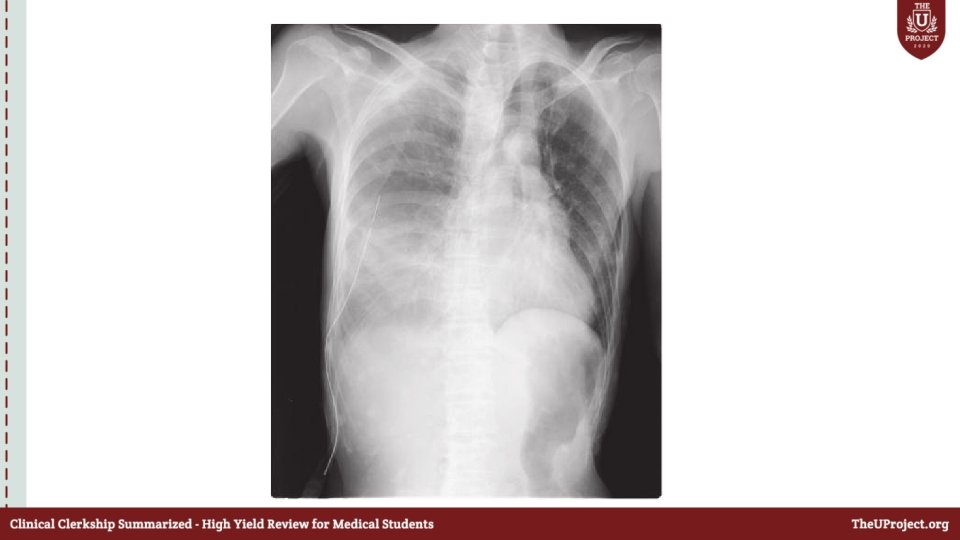

Case 3 • 25 year old man was stabbed in the chest while he was walking in the street. He was brought to ED by EMS. What will you do next ?

• A: Patent Will you keep the C-collar in place ? B: Sp. O 2 : 80% ; reduced air entry on the right side of the chest What will you do next ?

• Where will you place your ICD ? • What will you do next ?

• A: Patient is not responding What will you do ? • BP dropped to 80/40 ; what will you do ? • Type of blood ? • What will you do next ?

• Patient dropped his BP again to 70/40 mm. Hg ; what will you look for ? • What is the definition of massive hemothorax ?

• Chest tube drained 2 L of blood what will you do next ?